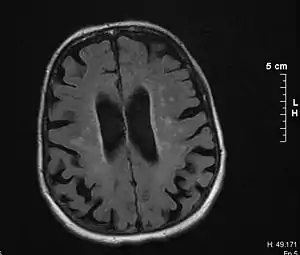

Binswanger's disease can usually be diagnosed with a CT scan, MRI, and a proton MR spectrography in addition to clinical examination. Indications include infarctions, lesions, or loss of intensity of central white matter and enlargement of ventricles, and leukoaraiosis. A Mini–Mental State Examination (MMSE) has been created to quickly assess cognitive impairment and serves as a screening test for dementia across different cultures.

Leukoaraiosis (LA) refers to the imaging finding of white matter changes that are common in Binswanger disease. However, LA can be found in many different diseases and even in normal patients, especially in people older than 65 years of age.[5]

There is controversy whether LA and mental deterioration actually have a cause and effect relationship. Recent research is showing that different types of LA can affect the brain differently, and that proton MR spectroscopy would be able to distinguish the different types more effectively and better diagnosis and treat the issue.[9] Because of this information, white matter changes indicated by an MRI or CT cannot alone diagnose Binswanger disease, but can aid to a bigger picture in the diagnosis process. There are many diseases similar to Binswanger's disease including CADASIL syndrome and Alzheimer's disease, which makes this specific type of white matter damage hard to diagnose.[5] Binswanger disease is best when diagnosed of a team by experts including a neurologist and psychiatrist to rule out other psychological or neurological problems.[3] Because doctors must successfully detect enough white matter alterations to accompany dementia as well as an appropriate level of dementia, two separate technological systems are needed in the diagnosing process.

Much of the major research today is done on finding better and more efficient ways to diagnose this disease. Many researchers have divided the MRIs of the brain into different sections or quadrants. A score is given to each section depending on how severe the white matter atrophy or leukoaraiosis is. Research has shown that the higher these scores, the more of a decrease in processing speed, executive functions, and motor learning tasks.[13][14] Other researchers have begun using computers to calculate the percentage of white matter atrophy by counting the hyper-intense pixels of the MRI. These and similar reports show a correlation between the amount of white matter alterations and the decline of psychomotor functions, reduced performance on attention and executive control.[15][16] One recent type of technology is called susceptibility weighted imaging (SWI) which is a magnetic resonance technique which has an unusually high degree of sensitivity and can better detect white matter alterations.[17]